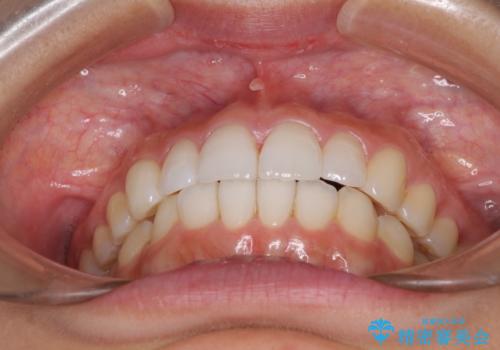

口が閉じにくい 1本飛び出した前歯の矯正治療

結婚式までに前歯を整えたいとのことでしたが、インビザラインでは先に奥歯を移動させてから前歯を動かすため、間に合わない可能性がありました。しかし、結婚式までに期間があったことと、マウスピースをしっかりと装着してくださったことで、十分な歯列に整えることができました。

楽しく通院していただき、辛いと思っていた治療もあっという間であったそうで、患者様には大変満足していただきました。